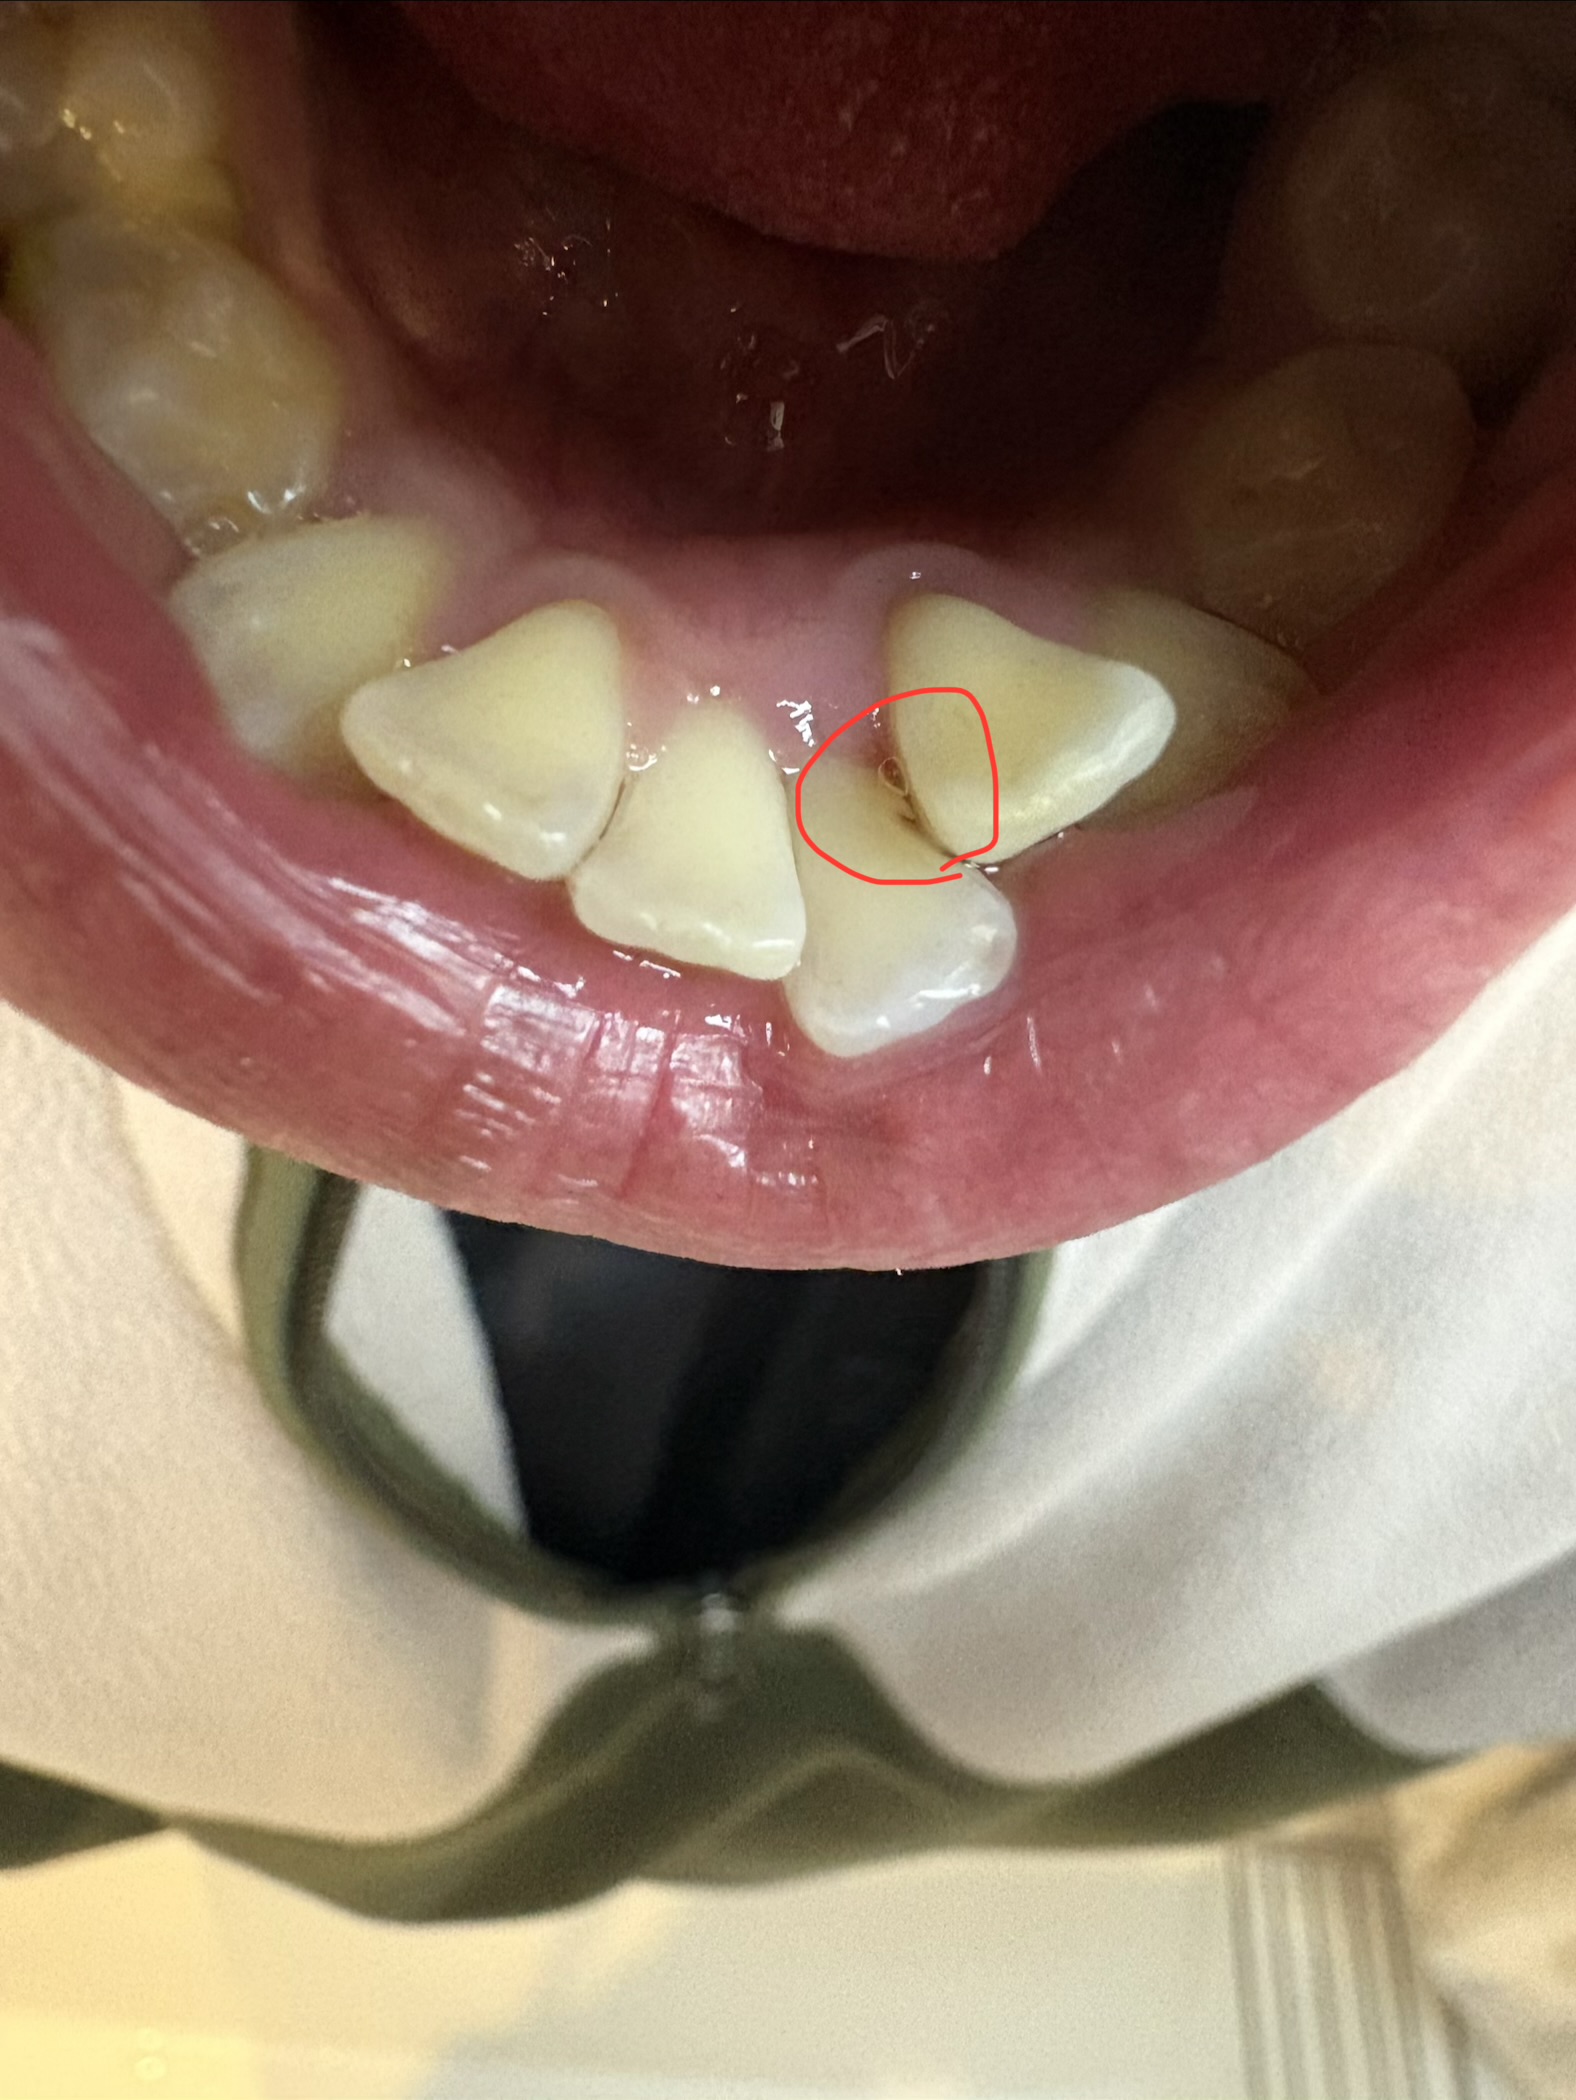

写真のように、切れ込みがあってフロスをすると少し引っかかるような段になっています。

これは削りすぎでしょうか?それともよくあることですか?